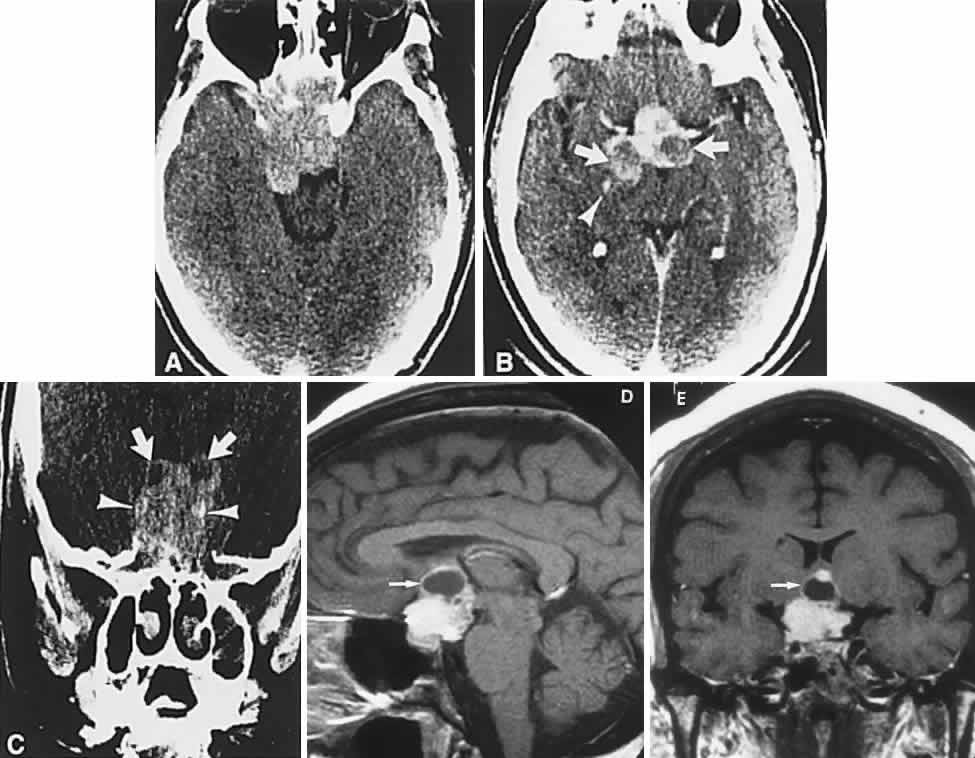

Endocrine-inactive tumors fail to produce clinical manifestations of any secretory product when a normal hormone is produced in amounts too small to be detected, when an abnormal hormone is produced but not recognized by biologic receptor sites or detected by radioimmunoassay, or when formerly endocrine-active cells have lost the ability to produce hormone as a result of degeneration. Of 1000 pituitary tumors surgically treated by Wilson,20 226 were endocrine-inactive, and 774 were secretory, as follows: PRL, 410; GH, 195; ACTH, 167; thyroid-stimulating hormone, 2. Nonsecretory adenomas, which consist mostly of null-cell adenomas, tend to be larger at presentation than do secretory tumors, with a median age of 57 years, and male predominance.21 Nonocular symptoms, as previously discussed, include chronic headaches (severe or mild) in more than two-thirds of patients,1 fatigue, impotence or amenorrhea, sexual hair change, or other signs of gonadal, thyroidal, or adrenal insufficiency. The typical sequence of hormonal deficiencies associated with large adenomas is early loss of GH and gonadotropin, later loss of thyrotropin and corticotropin. With the increasing application of neuroimaging and sensitive assays for abnormal hormones, the incidence of ophthalmologic presentation is decreasing, whereas the incidence of neuro-endocrine findings is increasing. Signs and symptoms, visual or otherwise, nonetheless may exist for months to years before so much as a visual field or plain skull film is obtained.4 Visual failure with pituitary tumors assumes a limited number of field patterns. As suprasellar extension evolves, a single optic nerve may be compromised, with resultant progressive monocular visual loss in the form of a central scotoma. More frequently, as the tumor splays apart the anterior chiasmal notch, superotemporal peripheral hemianopic defects occur. However, this well-touted superior bitemporal hemianopia is almost always accompanied by minor or major hemianopic scotomas approaching the fixational area along the vertical meridian (see Fig. 1). Asymmetry of field defects is the rule, the eye with the greater deficit likely showing diminished visual acuity. Marked asymmetry is not uncommon, such that one eye may be nearly blind while the other shows a temporal hemianopic defect (see Fig. 1C); this combination is as exquisitely localizing to the chiasm as is classic bitemporal hemianopia. Adenomas extending posteriorly produce incongruous hemianopias (see Fig. 5) by optic tract involvement; central vision is usually diminished, at least in the ipsilateral eye, and optic atrophy evolves. On extremely rare occasions, arcuate Bjerrum's scotomas extend from the blind spot into the nasal field22 or terminate at the vertical meridian.23 Such defects are usually monocular and are difficult to distinguish from glaucoma by perimetry alone. With progression, especially if the temporal field of the other eye becomes involved, a more typical field pattern evolves. In late stages of visual loss, the only suggestion of the chiasmal character of field defects may be minimal preservation of the nasal field of one eye (see Fig. 1C). The importance of serial examinations is obvious, but, when doubt exists, neuroimaging is mandatory. The absence of field defects, for example, in patients undergoing evaluation for amenorrhea, galactorrhea, or sellar enlargement incidentally discovered, does not imply the absence of an adenoma. Obviously, patients with microadenomas, that is, confined within the sella, do not have field defects. From a study24 of 50 cases of pituitary adenomas with chiasmal syndrome, it was concluded that visual disturbance occurs when the chiasm is displaced approximately 10 mm upward (see also Volume 2, Chapter 4, Fig. 6). The modern management of pituitary adenomas should involve several disciplines: current neuroradiologic studies detect microadenomas and provide precise delineation of gross morphology and status of neighboring structures, and mixed MRI signals suggest new or old hemorrhage, cysts, and so forth (Fig. 2); radioimmunoassay techniques assay PRL and other endocrine levels; oral neuropharmacologic agents, such as bromergocryptine, provide a “medical adenomectomy” for hyperprolactinemia and acromegaly; transsphenoidal surgery, including high-illumination microscopical procedures, televised radiofluoroscopic monitoring, and infection control, has all but replaced transcranial approaches; immunohistochemistry techniques have replaced the anachronistic tinctorial designations (e.g., chromophobe, basophilic) with a functional classification. PRL-secreting adenomas are the single most common type of pituitary tumor and occur more frequently in women than in men.20 Most of these tumors are microadenomas, although tumors confined to the sella are relatively rare in men. In women, amenorrhea and galactorrhea are the symptoms that provoke investigation, whereas in men, symptoms include loss of libido, impotence, gynecomastia, galactorrhea, and hypopituitarism.25 These various clinical manifestations occur with or without visual loss, depending on the volume of the adenoma; that is, the degree of suprasellar extension and compression of the chiasm. As a rule, true prolactinomas are associated with serum PRL levels higher than 150 to 200 ng/ml, and they usually range from 700 to 7000 ng/ml; the larger the tumor, the greater the serum PRL and, therefore, radiologically large adenomas with PRL levels lower than 200 ng/ml are probably nonsecreting and are not likely to respond to medical therapy (see below). Hyperprolactinemia up to 100 ng/ml may be due to simple physiologic causes, including stress, sexual intercourse, nipple stimulation, and exercise, or it may be secondary to pharmacologic agents such as phenothiazines, tricyclic antidepressants, calcium channel blockers, and cimetidine.25 However, other lesions in and around the pituitary gland and hypothalamus that compromise the pituitary stalk may present as “pseudoprolactinomas.” Immunohistochemical studies performed on 97 tissue specimens in patients operated on for presumed prolactinomas at the Mayo Clinic in Rochester, Minnesota26 revealed 65% to be microadenomas, but null-cell tumors accounted for 4 of 5 pseudoprolactinomas; these tended to be large at diagnosis, but with minor PRL elevation. Suprasellar cystic lesions can also cause hyperprolactinemia with field defects,27 as can carotid suprasellar aneurysms.28 Unlike true prolactinomas, non-PRL-secreting suprasellar tumors, with secondary hyperprolactinemia due to pituitary stalk compression, do not show a correlation between size and PRL level.29 With the advent of the ergot-derived dopamine agonist bromocriptine, there is a pharmacologic alternative (or adjunct) to surgery for prolactinomas. Bromocriptine (2-bromo-alpha-ergocryptine) is representative of a class of ergot derivatives that, since the early 1970s, have been known to inhibit pituitary gonadotropic function, reduce PRL secretion, and diminish the size of pituitary tumors (see Fig. 2). Such ergot derivatives are structurally related to dopamine, a PRL-inhibitory factor elaborated by hypothalamic dopaminergic neurons. It is likely that bromocriptine acts in two ways: dopamine turnover in tubero-infundibular neurons is depressed, thereby increasing hypothalamic dopamine; dopamine receptors of the pituitary are inhibited, reducing both spontaneous PRL secretion and the release of PRL provoked by thyrotropin-releasing hormone. At any rate, bromocriptine decreases PRL production and secretion, with resultant reduction in lactotrope size and subsequent diminution of tumor volume, often rapidly, within 1 to 2 hours of initiation of treatment.25 Spark and associates,30 among others, reported the efficacy of bromocriptine in reducing tumor size; it was demonstrated that bromocriptine lowered PRL, reduced GH in acromegaly, and reversed visual field defects. However, patients with extrasellar extension or with high PRL levels did less well. The great weight of evidence now clearly shows that most microadenomas (intrasellar) are demonstrably reduced in size,31 in about 3 months at an average dose of 5 mg per day, but cystic necrosis may develop, and adenomas may increase in volume if bromocriptine is discontinued. The tumor-reducing effect of bromocriptine on prolactinomas has been tested on 5 types of large, extrasellar pituitary tumors.32 Twenty patients were treated prospectively for up to 4.5 years with bromocriptine 30 mg or 60 mg per day (2 patients received 15 mg and 160 mg, respectively), and the effect on the size of the pituitary tumors was quantitated by planimetry of CT scans before and during treatment. The immediate success rate was 16 of 20 tumors, and 11 nonsecreting tumors were reduced by a median of 32%, with an immediate success rate of 9 of 11. Nine secreting tumors (4 that secreted PRL; 3, GH; 1, ACTH; and 1, thyroid-stimulating hormone) were reduced by a median of 51%. The reduction in tumor size was significantly associated with pretreatment volume, but not with the hormonal serum concentrations or with previous radiation treatment. Moreover, bromocriptine treatment did not cause any pituitary insufficiency other than the desired suppression of PRL. The clinical course of 10 patients with macroprolactinomas at the Wills Eye Hospital in Philadelphia was carefully documented33 after treatment with bromocriptine in daily doses ranging from 7.5 to 30 mg. Nine patients enjoyed improvement in acuity and fields quite rapidly, often within a few days, including the following: hand movements to 20/20 within 1 month, counting fingers to 20/20 or 20/30 within 7 to 12 days, and dramatic recovery of field defects. There was also a demonstrable decrease in tumor size by CT criteria, and lowering of serum PRL. Four patients subsequently required transsphenoidal decompression, for conditions including failure of visual improvement, cerebrospinal fluid (CSF) rhinorrhea, and medication intolerance. The authors cautioned that the long-term effects of bromocriptine therapy are not known, and prompt tumor regrowth is to be anticipated when the drug is discontinued. It was recommended that patients who are to undergo surgical decompression should be treated preoperatively to decrease tumor size and “to facilitate surgical removal,” and that residual tumor with elevated PRL should be treated with bromocriptine. A similar patient34 with a large pituitary tumor, hyperprolactinemia, bitemporal fields defects, and invasion of one cavernous sinus (involving the fifth and sixth cranial nerves) was treated with bromocriptine 7.5 mg per day,35 with marked reduction in the tumor size and resolution of field defects and cranial nerve dysfunction over a 6-month period, at which point the sella appeared empty. Other dopamine agonists are available or under investigation, including long-acting bromocriptine (Parlodel), cabergoline, and CV-205-502; some prolactinomas resistant to standard dopamine agonists may respond to more potent agents such as cabergoline.35 Ophthalmic results in patients with macroprolactinomas treated with dopamine agonists show generally good results, with few instances of pituitary necrosis.25,36 Indeed, it may be that these newer pharmaceuticals should be the treatment of choice in patients with large pituitary tumors with extrasellar extensions. These unquestionable successes notwithstanding, there remain unanswered questions concerning dopamine agonist therapy: Is long-term medical therapy preferable to simple transsphenoidal surgery? Can such patients ever be weaned from medical therapy? What about the ultimate outcome of tumors not characterized by PRL secretion? Should large, asymmetric (invasive?) adenomas be pretreated to make surgical removal easier? Based on an extensive experience, Wilson20 recommended microsurgical transsphenoidal removal of macroprolactinomas, with presurgical bromocriptine treatment of tumors larger than 2 cm. The details of neurosurgical procedures are beyond the scope of this present work, but Wilson's review and other sources37 should be consulted. Varying within the spectrum of surgical experiences, complications of transsphenoidal procedures include anterior pituitary insufficiency (about 20%), diabetes insipidus (about 18%), CSF rhinorrhea (about 4%), and, rarely, loss of vision or diplopia.38 Infrequent untoward results include hydrocephalus secondary to subarachnoid blood, cerebral ischemia related to vasospasm, meningitis with or without CSF leak, and death associated with intraoperative or postoperative hemorrhage.20,38 Radiation therapy is currently used as an integral part of postoperative treatment in patients with incompletely resected nonfunctional adenomas. External-beam conventional protocols delivering median total dosage of 45 Gy are considered highly effective in preventing recurrence of hormonally inactive tumors, but they may compound relative hypopituitarism.39 Young patients with total tumor removal, or without MRI evidence of recurrence, may be safely observed with radiation therapy held in reserve. The role of stereotactic radiosurgery (single-fraction high-dosage) of pituitary adenomas is not yet clear, preliminary results notwithstanding.40 Following uncomplicated surgical decompression, visual acuity and fields may return with dramatic speed or improve weekly. Such restoration is dependent on duration of visual morbidity and, to some extent, the degree of pallor of the optic discs. Preoperatively, if careful ophthalmoscopy reveals attrition of the retinal nerve fiber layer, corresponding field defects are permanent. For the most part, what vision returns does so by 3 to 4 months, if not sooner, but many months may pass before maximum recovery is attained. Not all surgical procedures are successful, and visual function may worsen, especially after frontal craniotomy for large adenomas with massive suprasellar extension. Visual deterioration at or immediately following surgery is related to intrasellar hematoma formation, edema of tumor remnants, or direct surgical manipulation of optic nerves or chiasm and adjacent vasculature. Arterial injuries, for example, 21 instances in more than 1800 cases, produce intraoperative hemorrhage, delayed epistaxis, carotid arterial occlusion, and pseudoaneurysm.41 Postoperative packing of the sella with muscle or subcutaneous fat may compress the optic nerves and chiasm, for which reason MRI is warranted when vision is worsened or does not recover quickly within a few days.42 After surgical, medical, or radiation therapy, the visual fields should be assessed as soon as possible to determine baseline function. In uncomplicated cases, monthly intervals during the first 3 months should suffice, then at 6 months, and subsequently yearly follow-up are usually adequate. Recurrence of visual failure may be caused by regrowth of tumor, arachnoidal adhesions associated with a progressive “empty sella syndrome” (see below), or delayed radionecrosis (see below). Tumor recurrence is by far the most common mechanism of visual deterioration, but field examination alone may not make this distinction. With prolactinomas, serum PRL levels may be monitored, and, indeed, prolactinomas have a higher recurrence rate than nonsecreting tumors.43 Although it is not known for certain which factors influence risk of recurrence, certainly the original size of the tumor does, as well as PRL activity. In one series,44 the rate of recurrence in 56 patients with large adenomas, all but 1 having received postoperative irradiation, was 20% (11/56), occurring between 6 months and 6 years. Again, it was not clear that original tumor size was related to more aggressive growth or high recurrence rate, but no histologic differences were found between tumors that were large and relapsing and those that were smaller and did not recur. In another series45 of 100 nonfunctioning pituitary tumors, of which 82% were null-cell adenomas, symptomatic recurrence developed in 6 patients, and 10 demonstrated radiographic recurrence during 48 to 100 months (mean, 73.4 months) of observation after transsphenoidal surgery; the effect of radiation therapy was moot. The follow-up of treated adenomas has been problematic, from the standpoint of detecting recurrence. As adenomas must be large initially to cause visual defects, so must recurrences be substantial before defects again evolve. Although progressive visual failure may be the incontestable impetus for re-operation or irradiation, consecutive perimetry may not be counted on to reveal “early” tumor recurrence. An anatomic assessment, as provided by CT scanning or MRI with coronal views, provides the most sensitive technique for monitoring tumor regrowth. In addition, measurement of serum PRL levels in the immediate postoperative period and at regular intervals is a rational way to determine recurrence of prolactinomas. Pituitary adenomas may act more aggressively on occasion, invading the laterally adjacent cavernous sinuses and producing acute or chronic cranial nerve palsies (see Volume 2, Chapter 12). Potential markers for aggressive biologic behavior include p53, MIB-1, PCNA, RB, and H-ras; a high MIB-1 antibody index indicates active proliferation, as does positive p53.46 Indeed, prolactinomas may metastasize. A case of “sinusoidal adenoma” invading the skull base, pterygoid, and orbit of a 12-year-old boy was reported47; the cytologic picture suggested “a higher degree of malignancy than usual,” but it did not appear to be an undifferentiated carcinoma. Another rare instance of an invasive pituitary adenoma was described also in a 12-year-old boy who presented with severe headache, vomiting, rapid loss of monocular acuity, and sixth nerve palsy48; histologically, there was absence of cellular pleomorphism or of mitosis despite the invasive course. Histologic criteria apparently are not sufficient to indicate invasive tendencies, and local extension is not evidence of malignancy. Seeding of the subarachnoid space and spread outside the cranium are extremely rare complications that indicate biologic malignancy. Malignant lesions of the pituitary may be initially mistaken for simple adenomas, including sellar plasmacytoma, lung, and breast metastases49; atypical features suggesting malignancy include rapidly progressive visual loss, ocular motor palsies, and facial numbness (see also below, Metastatic Diseases and Other Mass Lesions). In addition, benign and rare vascular malformations of the sella fossa are reported.50 ACROMEGALY Other adenomas secrete ACTH or thyroid-stimulating hormone or are “mixed” (most commonly PRL- and GH-secreting), but they are principally of endocrinologic interest and relate to neuro-ophthalmology only when extrasellar extension produces field defects. However, acromegaly requires further elaboration. Acromegaly is the clinical condition associated with excess GH either from autonomous pituitary adenoma secretion or from hypothalamic production of GH-releasing factor with subsequent GH hypersecretion. Many GH-secreting tumors contain a mutant form of the chain of GS protein in the somatotrope. This represents a relatively rare endocrinopathy, although in Wilson's surgical series20 of 1000 transssphenoidal procedures, there were 195 cases of GH-secreting adenomas, and 228 cases of acromegaly were found among 1000 adenomas seen at the Mayo Clinic from 1935 to 1972.51 Clinical features include bone and soft tissue enlargement, especially of hands, feet, and face, visceromegaly, arthritis and carpal tunnel syndrome, hypertension, diabetes, hyperhidrosis, weakness, arthralgias, tooth malocclusion, headaches, impotence, menstrual irregularities, and abnormal glucose tolerance test results. Adenomas associated with acromegaly seem not to expand beyond the sella with the regularity typical of prolactinomas or nonsecretory tumors. This phenomenon may be attributable to earlier detection as a consequence of prominent clinical manifestations. Nonetheless, 144 of 228 patients with acromegaly in the Mayo Clinic series51 had visual field defects, a finding that may reflect delay in diagnosis in a series commenced 6 decades ago. The use of octreotide and other long-acting analogs of somatostatin are indicated as follows: for the treatment of patients with active disease when surgery or radiation therapy has failed or is contraindicated; while awaiting the clinical effects of radiation therapy; as primary treatment in the elderly and medically incapacitated.52 Long-term octreotide therapy reduces serum levels of GH and insulin-like growth factor-1, and it reduces tumor size.53 Ablation of GH-adenomas is also achieved with various forms of radiation therapy, but more or less immediate remission is best accomplished by transsphenoidal resection. PITUITARY “APOPLEXY” Pituitary “apoplexy” refers to an acute change in volume of a pituitary adenoma as a result of spontaneous hemorrhage, edematous swelling, or necrosis. Postpartum infarction or hemorrhage in nontumorous glands does occur, as firmly established in the obstetric literature as “Sheehan's syndrome,”54 but chiasmal compression is a rare event. Even in clinically silent cases, adenoma necrosis with cystic liquefaction and evidence of previous bleeding is encountered commonly enough and may be identified by radiologic criteria (see below). Gross or microscopic hemorrhagic necrosis is apparently independent of endocrine activity or neoplastic pattern. In a review55 of 320 verified adenomas, with a high incidence in giant or recurrent large adenomas (41%), evidence of hemorrhage was found in 58 cases (18%). Mean age was 50 years, and clinical courses included the following: acute apoplexy, 7 cases; subacute apoplexy, 11 cases; recent silent hemorrhages, 13 cases; old silent hemorrhage, 27 cases. That is, in 58 cases of hemorrhage in adenomas, 40 were symptomatically silent. From a series56 of 453 operated adenomas, 45 (10%) demonstrated hemorrhage, but only 13 of these patients had acute symptoms of pituitary apoplexy; the authors correlated hemorrhage with marked suprasellar extension. Wilson20 concluded that most massive pituitary tumors are prolactinomas, and there is “evidence of necrosis in most prolactinomas”; spontaneous necrosis or hemorrhage is related to indolent tumor growth; that is, tumor cell population expands or contracts at a rate determined by the balance of cell production and cell death. Hemorrhage into adenomas is documented following head trauma,57 after cardiopulmonary bypass,58 and subsequent to tests of pituitary function using thyroid-releasing hormone, gonadotropin-releasing hormone, and insulin.59 Additionally, uncomplicated pregnancy, bleeding disorders, radiation therapy, adrenalectomy, and physical exertion are all reported predisposing factors in pituitary “apoplexy.”60 Indeed, pituitary hemorrhage may occur in adolescence,61 principally in prolactinomas. Clinical signs and symptoms include the following: acute onset of severe headache, often sickening frontal or retro-bulbar cephalgia, or other less disabling change in headache pattern; acute or rapidly progressing unilateral or bilateral (usually asymmetric) ophthalmoplegia due to rapid expansion into cavernous sinuses (see also Volume 2, Chapter 12); epistaxis or CSF rhinorrhea when the mass ruptures or erodes into the sphenoid sinus; complications of blood or necrosis debris in the CSF, with “pseudomeningitis”; rapid neurologic deterioration and obtundation, although patients need not be stuporous; and, greater or lesser degrees of hypopituitarism.62,63 Selective expansion laterally into the cavernous sinus may produce ophthalmoplegia without visual loss; selective expansion superiorly may produce visual loss without ophthalmoplegia. Almost without exception, enlargement of the sella is found even on plain skull film views; both CT and MRI detect fresh hemorrhage (Fig. 3), but MRI may fail to demonstrate acute hemorrhage unless specific sequences are employed (hemorrhage may be isointense on T1-weighted images and hypointense on T2-weighted images; in the subacute phase, extracellular methemoglobin should appear bright on both T1 and T2 sequences). Corticosteroid replacement and other supportive measures may be critical, and, in most instances, decompression through the sphenoid sinus is advisable, sooner rather than later. Bromocriptine has been suggested as a temporizing measure when signs and symptoms are modest and not progressing,64 and there are advocates65 for conservative management consisting of intravenous dexamethasone, so long as visual deficits are minimal or rapidly improve; otherwise decompressive surgery is required. Given the regularity with which pituitary apoplexy is often a delayed diagnosis, being confused with ruptured aneurysm or meningitis, for example, and that transsphenoidal surgery is a relatively simple undertaking, further procrastination in decompression of the compromised visual pathways is to be avoided. Imaging of Pituitary Tumors In addition to the radiologic implications mentioned previously, specific points should be emphasized. Contrast-enhanced CT and, especially, MRI have replaced all previous radiologic techniques in the detection and anatomic assessment of sellar and juxtasellar lesions. MRI has also the inherent advantage of using no radiation, nor does it require iodinated contrast injections. Although thin-section contrasted CT does indeed disclose most lesions, bone changes, and recent hemorrhage, MRI is superior in delineating distortions of optic nerves and chiasm, in displaying arteries, and in revealing fat, hemorrhage, or cyst (see Figs. 3E through M). Indeed, in a prospective study of normal volunteers, gadolinium-enhanced MRI disclosed pituitary adenomas (3 mm to 6 mm in diameter, i.e., microadenomas) in 10% of adults aged 18 to 60 years.66 T2-weighted fast spin-echo MRIs are currently the most precise sequence for demonstrating the optic nerves and chiasm, even when these structures are severely distorted by suprasellar tumor extension.67 The question of invasion or displacement of the cavernous sinus has been studied by MRI technique,68 with the following conclusions: the normal cavernous sinuses are usually symmetric but vary in size; the lateral dural margins are easily recognized as linear, discrete, low-intensity structures; the medial dural margin (pituitary capsule) is rarely discernible; sensitivity of predicting cavernous sinus invasion is only 55%; no features permit certain distinction between invasive and noninvasive adenomas, because the medial wall of the cavernous sinus is not reliably identified; the most specific sign of invasion is carotid artery encasement. Normal pituitary glands extend laterally into the cavernous sinus in 29% of microanatomic dissection specimens.69 A study70 of the CT appearance of pituitary masses after transsphenoidal surgery showed that the superior limits do not return to normal immediately despite complete tumor removal, but only gradually regress in 3 to 4 months. This phenomenon is variably due to blood clot in the sella, to muscle or fat used as packing material, and to adhesions between the diaphragma sellae or tumor and brain tissue above. Therefore, neuroimaging in the immediate postoperative period may be misleading, and baseline radiologic evaluation may be delayed for 3 to 4 months, unless otherwise indicated. MENINGIOMAS Posterior perioptic foraminal, medial sphenoid ridge, and tuberculum sellae meningiomas produce prechiasmal (optic nerve) or chiasmal compression, as do olfactory groove and planum masses that extend posteriorly. Visual deficits usually take the form of slowly progressive monocular loss of vision, and, when both fields are involved, there is a distinct tendency toward marked assymetry, frequently with extensive visual deficit on one side before the contralateral field becomes involved. Slow growth across the tuberculum eventuates in contralateral optic nerve or chiasmal interference. There is a distinct predilection for meningiomas to occur in middle-aged women, and enlargement during pregnancy, as well as possible association with breast cancer, supports evidence for the role of estrogen and progesterone receptors.71 Although nonspecific headaches are a common feature of suprasellar meningiomas, most patients present with monosymptomatic failure of vision and are thus likely to present initially to the ophthalmologist. Although relentless deterioration of vision is the rule, fluctuations over weeks or months may mimic optic neuritis.72 Slavin73 documented an exceptional case of acute, bilateral central scotomas developing over 2 weeks, in the presence of a gigantic meningioma that extended into the ethmoid sinuses and under the frontal lobes. In a series of suprasellar meningiomas,74 the time interval from the onset of unilateral visual loss to subjective bilateral defects, was 1 to 8 years; simultaneous bilateral onset was not documented. Although periocular pain made worse by eye movement is typical of inflammatory optic neuritis, Ehlers and Malmros75 reported this symptom with suprasellar meningiomas. Asymmetric optic disc pallor is a relatively “late sign,” normal discs being fully compatible with visual loss over many months. The much-touted Foster Kennedy syndrome, that is, optic atrophy with contralateral papilledema due to large subfrontal meningiomas, remains a distinct rarity.75 Anosmia, also classically considered an important finding with olfactory meningiomas, is much overrated and is difficult to assess. Delayed diagnosis of large tumors results in frontal lobe compression and edema causing mental changes or hydrocephalus due to obstruction of the ventricular system. In previous decades, chiasmal interference with optic atrophy, but “normal” plain skull films, was referred to as “Cushing's syndrome of the chiasm,” caused by meningiomas, aneurysms, or other noncalcified suprasellar lesions. The modern neuroimaging techniques of enhanced CT, “bone-window” protocols, and gadolinium-contrasted MRI are now exceedingly sensitive in disclosing meningiomas or other parachiasmal masses (Fig. 4). At present, contrast-enhanced CT or MRI precisely demonstrate extra-axial tumor configuration; CT is superior in disclosing calcification or bone changes, but it is inferior for assessing suprasellar or intrasellar extension, postsurgical changes, and vascular displacement or encasement.76 Whether MRI or even MR angiography obviates standard selective arteriography, especially when surgical intervention is contemplated, is moot. In a large surgical series,77 257 patients underwent 338 craniotomies for meningiomas at diverse intracranial locations. Of these, there were 35 sphenoid wing, 20 olfactory groove, 12 tuberculum sellae, and 2 orbito-cranial meningiomas; that is, about 27% of tumors were of potential neuro-ophthalmologic interest. For the entire series, average observed survival was 9 years, and recurrence rate was 22% overall. At the Massachusetts General Hospital in Boston,78 of 225 patients operated on for meningioma, parasellar tumors constituted 12%; only half of these were considered grossly “completely excised,” but with a 5-year probability of recurrence or progression of 19%. No radiation therapy was applied in this series. Rosenberg and Miller79 analyzed the visual results in 16 patients following modern microsurgical removal of meningiomas involving the intracranial optic nerves or chiasm. Median age at diagnosis was 56.5 years, and median duration of visual symptoms was 19.5 months. Visual acuity improved in 12 of 32 eyes, worsened in 8 (3 optic nerves were transected; 5 eyes showed an average drop of 2.6 lines in acuity), and 10 eyes retained normal function. Visual outcome appeared to be related most closely to duration of symptoms. The response of meningiomas to irradiation has not been clearly established. In general, growth and regrowth rates are extremely slow, compounding the problem of assessing the question of radiotherapeutic efficacy. In a series of 12 incompletely resected meningiomas (8 sphenoidal, 2 petrosal, 1 each orbital and parasagittal), patients were subjected to 4800 to 6080 cGy (median dose, 5490 cGy) in 6 weeks80; median postradiation follow-up was 54.5 months (range, 20 to 120 months), and 9 patients were said to remain free of clinical or radiologic signs of tumor progression. Recurrent lesions were discovered at 4, 6, and 9 years, and the authors concluded that postoperative radiation therapy is indicated for incompletely excised meningiomas. Carella and colleagues81 reviewed the experience with 68 patients, 49 women and 19 men, divided into 3 groups: (A) 43 patients who had surgery (42 with known residual tumor) followed by irradiation; (B) 14 patients who had radiation for recurrence, of whom 11 underwent subtotal resection before radiation therapy; (C) 11 patients who had radiation as primary treatment. In Group A, 41 of 43 patients were alive, most doing well neurologically after 1 to 10 years; in Group B, 5 were dead of meningioma (all within 3 years), and 7 patients were considered “stable”; in Group C, all were alive at 3 to 6 years, 9 with neurologic improvement, and 4 with CT evidence of tumor shrinkage with central necrosis. Conventional fractionated radiation therapy continues to provide mixed results,82,83 and stereotactic radiation therapy with single-fraction dosage has enthusiastic advocates, but relatively short-term follow-up data.84 Undoubtedly, external-beam radiation therapy has a role as an effective adjunctive treatment in the control of meningioma recurrence, but the possibility of collateral damage, including radionecrosis (see below) of vital neural structures, must be considered. With reference specifically to results of radiation therapy of meningiomas involving the anterior visual pathway, Kupersmith and coworkers85 analyzed 4 patients treated by irradiation alone and 16 treated in combination with tumor excision. Improvement in visual function occurred in 13 patients, 2 showed temporary improvement, and 5 maintained stable function for up to 9.5 years; follow-up CT did not disclose reduction in tumor size. The study by Kennerdell and associates,86 dealing primarily with optic nerve sheath meningiomas, inferred a distinct salutary effect of irradiation alone or as a supplement to partial microsurgical resection. The management of menigiomas involving the intracranial optic nerves and chiasm may be summarized as follows: surgery remains the principal initial endeavor, in some instances with efforts intended only at judicious gross “debulking”; postoperative radiation therapy at least appears to increase the recurrence-free interval in cases of incompletely resected tumors; radiation therapy alone (dosage range, 5000 to 5500 cGy) is an acceptable alternative in patients considered poor surgical risks, especially where tumor has encased major arteries or invaded the skull base or when neuroimaging demonstrates surgically inaccessable optic nerves or chiasm. Complications arise when adhesions of tumor to portions of nerves or chiasm, or to vessels, are agressively manipulated in attempts at “complete removal.” Progesterone receptor sites are expressed in 81% of women and 40% of men with meningiomas,71,84 with 96% of benign and 40% of malignant meningiomas containing progesterone receptor-positive nuclei, but without correlation between progesterone receptor index and age or histologic subtype.71 Moreover, the efficacy of antiprogesterone agents such as mifepristone has proved disappointing.87 At present, immunotherapy in the form of interferon-alpha is under investigation.88 Treatment options, or the absence thereof, must be considered in light of the glacial growth rate of most meningiomas. For example, Olivero and colleagues89 found that 78% of 60 asymptomatic meningiomas followed for over 2.5 years demonstrated no growth, and the remaining 22% showed a mean growth rate of only 0.24 cm in maximum diameter per year. Therefore, judicious observation may prove the best option, especially in the elderly or in patients with considerable risk for surgical intervention. Recurrence or regrowth of tumor is best monitored by contrast-enhanced CT and gadolinium-enhanced MRI. After initial postoperative baseline visual field plotting, consecutive perimetry discloses visual failure only as a relatively late sign of tumor enlargement. Perioptic meningioma of the intraorbital portion of the optic nerve is considered in Volume 2, Chapter 5, Part II. CRANIOPHARYNGIOMAS Craniopharyngiomas are tumors that arise from vestigial epidermoid remnants of Rathke's pouch, scattered as cell rests in the infundibulo-hypophyseal region. These tumors are usually admixtures of solid cellular components and variable-sized cysts containing oily composites of degenerated blood and desquamated epithelium or necrotic tissue (and blood) with cholesterol crystals. Dystrophic calcification of this debris is detectable with plain films and CT imaging and is an important radiologic sign estimated to be seen in more than 80% of childhood craniopharyngiomas. These tumors are congenital (dysontogenic) and, in rare instances, may present in the neonate. There is a more or less bimodal age incidence, peaking in the first 2 decades and again in the years 50 to 70 (Fig. 5). These predominantly suprasellar tumors account for 2% to 4% of all intracranial tumors regardless of age group, but the incidence is 8% to 13% in children. Of all suprasellar masses, craniopharyngiomas comprise 54% in children, and 20% in adults, and show two clinicopathologic and pathogenetic separate types: adamantinous (predominantly cystic, in childhood) and squamous-papillary (predominantly solid, adulthood).90 Presentation in childhood is commonly related to hydrocephalus and endocrinopathies, consisting of variable degrees of hypopituitarism with or without diabetes insipidus; obesity and somnolence also attest to hypothalamic disturbance. Gonadotropic hormone deficit results in retarded or absent sexual development, and precocious puberty is rare. In children, progressive visual loss goes unnoticed until a level of severe bilateral impairment is reached, or unless headache, vomiting, and behavioral changes occur. Increased intracranial pressure produces papilledema in about 65%, and optic atrophy is observed in roughly 60%.91 In adults, visual deterioration is the universal symptom that demands investigation, although occult endocrine dysfunction may be uncovered; hypopituitarism, diabetes insipidus, amenorrhea, and galactorrhea inconstantly eventuate. Visual field defects are frequently asymmetric bitemporal hemianopias or a homonymous pattern with reduced acuity (Fig. 6) when the optic tract is compressed.92 CT scanning retains special relevance to craniopharyngioma diagnosis, currently superior to MRI in detection of calcification and cyst formation (Fig. 7A to C); however, the extent of involvement of adjacent structures, that is, the optic chiasm, third ventricle, and intracavernous carotid artery, is more clearly delineated by MRI (Fig. 7D and E).93 Craniopharyngioma fluid collections are found to be uniformly bright on T2-weighted sequences, but on T1-weighted images, the signal intensity may range from hypointense to hyperintense, reflecting the heterogeneous contents of cysts. Because calcification and cyst formation are hallmarks of craniopharyngiomas, CT is more specific than MRI. At times, intrinsic infiltration of tumor may thicken the chiasm and contiguous optic nerve, a radiologic configuration that mimics glioma.94 Likewise, glioma may be simulated when the optic canal is invaded and enlarged, but accompanying bony erosion of the sella weighs heavily toward craniopharyngioma. More than half a century ago, Harvey Cushing declared that craniopharyngiomas “offer one of the most baffling of surgical problems,” and were “disheartening from an operative standpoint.”95 Fortunately, in the modern era, the surgical microscope, steroid replacement, radiation therapy, and valve-regulated shunts have all proved valuable adjuncts to the operative management of these masses. Since the time of Matson, a major neurosurgical school of thought was preoccupied with “complete” removal of craniopharyngiomas in preference to subtotal extirpation. Although primary total removal is no doubt ideal, this is actually only rarely accomplished. The question of “matsonian total removal” was addressed in the 1975 follow-up by Katz,96 who analyzed the results of surgical management in 51 of Matson's patients operated upon between 1950 to 1968; there was a 25% operative mortality, a 71% 11-year mortality, and 76% of those cases examined by autopsy had residual tumor at the time of death. A less ambitious approach consists of cyst aspiration, intracapsular dissection, cyst drainage via subcutaneous reservoir, and radiation therapy. In a series of 43 children at the Columbia-Presbyterian Medical Center in New York from 1952 to 1977,97 10-year actuarial survival rates were 52% for subtotal resection alone and 87% for subtotal plus radiation (mean, 5000 cGy). Tumors had recurred by 10 years in half of 14 children in whom removal was thought to be total, in more than 90% of those whose tumors were subtotally removed, and in less than 25% of those at risk after subtotal resection and irradiation. Recurrences were usually evident within 2 years, but more delayed after “total” resections. From a later series of 37 children cared for at Children's Hospital, Boston, from 1972 to 1981,98 it was concluded that radiation therapy was equally, if not more, effective than attempted excision in controlling subsequent tumor growth. It is inferred that conservative surgery combined with irradiation (mean dose, 5464 cGy) offers less risk for psychosocial impairment than does tumor excision, although the delayed effects of radiation to the juvenile brain must be taken into account (see the discussion of therapy for optic glioma, below). Craniopharyngiomas that arise low on the hypophyseal stalk are subdiaphragmatic and may be approached via the transsphenoidal route99; cystic recurrences may also be managed by transsphenoidal drainage, although surgical cure is unlikely. Interestingly enough, the first craniopharyngioma operated on successfully was reported in 1910, by Halstead, via the transsphenoidal approach.100 Regardless of surgical approach or use of radiation therapy, endocrine replacement is anticipated in all cases, often for life. OPTIC AND HYPOTHALAMIC GLIOMAS As noted in Volume 2, Chapter 5, Part I, astrocytic tumors of the anterior visual pathways present as two unrelated pathologic entities: the relatively benign and stable piloid glioma of childhood and the rare malignant glioblastoma of adulthood. Clinically and histologically, these two neoplasms have little in common, and the assumption that the malignant form stems from the indolent childhood glioma is untenable. The major clinical characteristics of these astrocytomas are contrasted in Table 1.